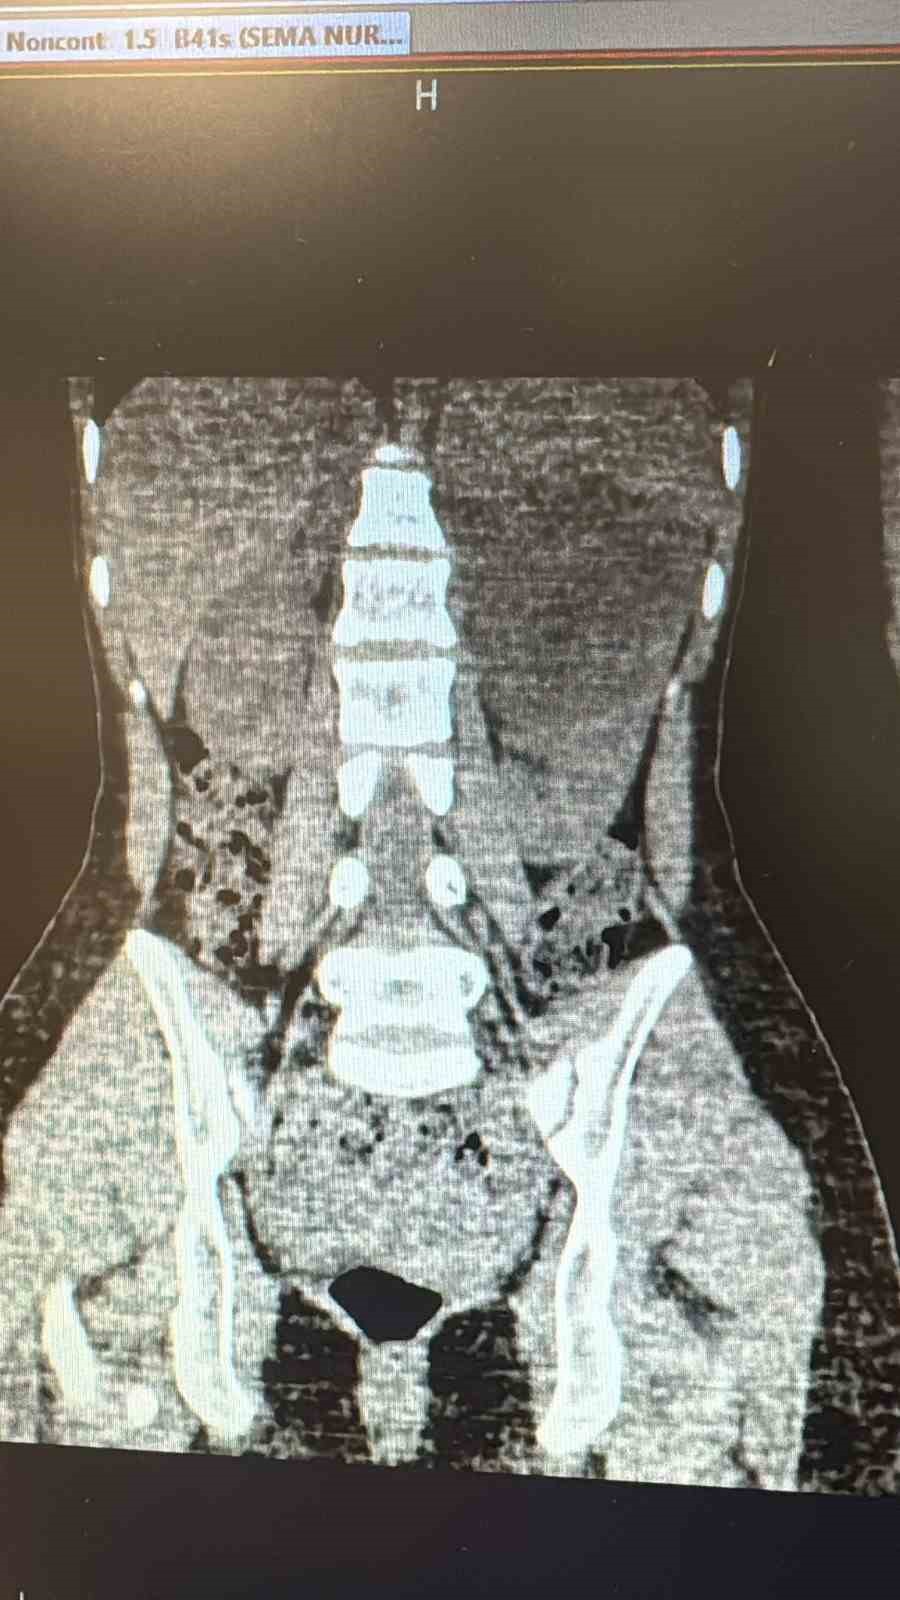

Şanlıurfa Viranşehir Devlet Hastanesi’nde, 18 yaşındaki bir hastanın sol böbreğinde tespit edilen yaklaşık 10 santimetre çapındaki kist, laparoskopik (kapalı) yöntemle başarıyla çıkarıldı.

Uzun süredir sol yan ağrısı şikâyeti bulunan kadın hasta, dış merkezde yapılan tetkiklerde sol böbrekten kaynaklanan, böbrek ve dalağı iterek komşu organlara yapışıklık gösteren büyük bir kist tespit edilmesi üzerine Viranşehir Devlet Hastanesi’ne sevk edildi. Hastanede yapılan değerlendirmelerin ardından kistin cerrahi yöntemle alınmasına karar verildi. Üroloji kliniğinde gerçekleştirilen operasyonda, 10 santimetre boyutundaki böbrek kisti laparoskopik yöntemle, 2 adet 5 milimetre ve 1 adet 10 milimetrelik kesi kullanılarak çıkarıldı. Böylece hasta, açık cerrahiye gerek kalmadan tedavi edildi. Ameliyat sonrası takiplerinde herhangi bir komplikasyon gelişmeyen hasta, sağlığına kavuşarak taburcu edildi.